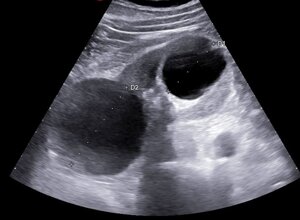

ECOGRAFIA ADDOME